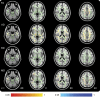

Methods: Fifty-three patients were scanned an average of 6 days postinjury (range = 1-14 days). Twenty-three patients were rescanned 1 year later. Thirty-three matched control subjects were recruited. At the time of scanning, participants completed cognitive testing. Tract-Based Spatial Statistics was used to conduct voxel-wise analysis on diffusion changes and to explore regressions between diffusion metrics and cognitive performance.

Results: Acutely, increased axial diffusivity drove a fractional anisotropy (FA) increase, while decreased radial diffusivity drove a negative regression between FA and Verbal Letter Fluency across widespread white matter regions, but particularly in the ascending fibers of the corpus callosum. Raised FA is hypothesized to be caused by astrogliosis and compaction of axonal neurofilament, which would also affect cognitive functioning. Chronically, FA was decreased, suggesting myelin sheath disintegration, but still regressed negatively with Verbal Letter Fluency in the anterior forceps.